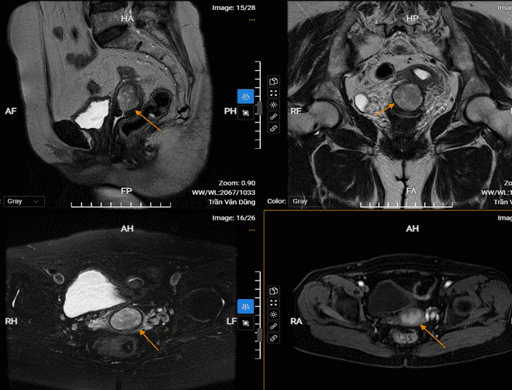

Chụp MRI tử cung phát hiện bệnh gì

Người mắc các bệnh lý về tử cung - phần phụ thường tự mua thuốc điều trị tại nhà, điều này có thể dẫn đến nhiều hậu quả nghiêm trọng, thậm chí gây ảnh hưởng đến khả năng sinh sản. Vì thế, việc nhận biết và chẩn đoán sớm bệnh lý tử cung - phần phụ là yếu tố quyết định trong điều trị khỏi hoàn toàn...